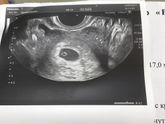

Наконец то!17 августа 2017 09:50 Привет девочки)) теперь и я с вами! Вчера наконец то увидела две полосочки?